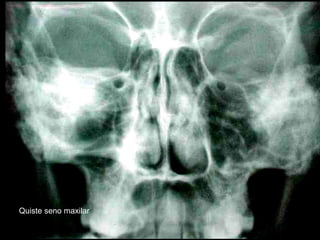

Quiste seno maxilar